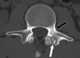

Sclerotic pedicle

Wilkinson's syndrome (also known as Sclerotic pedicle sign) is a radiographic term which describes a unilaterally enlarged pedicle opposite a contralateral pars defect. The enlarged pedicle may due to stress hypertrophy, and changes may extend into the adjacent lamina and transverse processes.The characteristic radiographic feature of Wilkinson's syndrome is a missing pedicle with a thick, sclerotic contralateral pedicle at the same level. [Source: Wikipedia ]